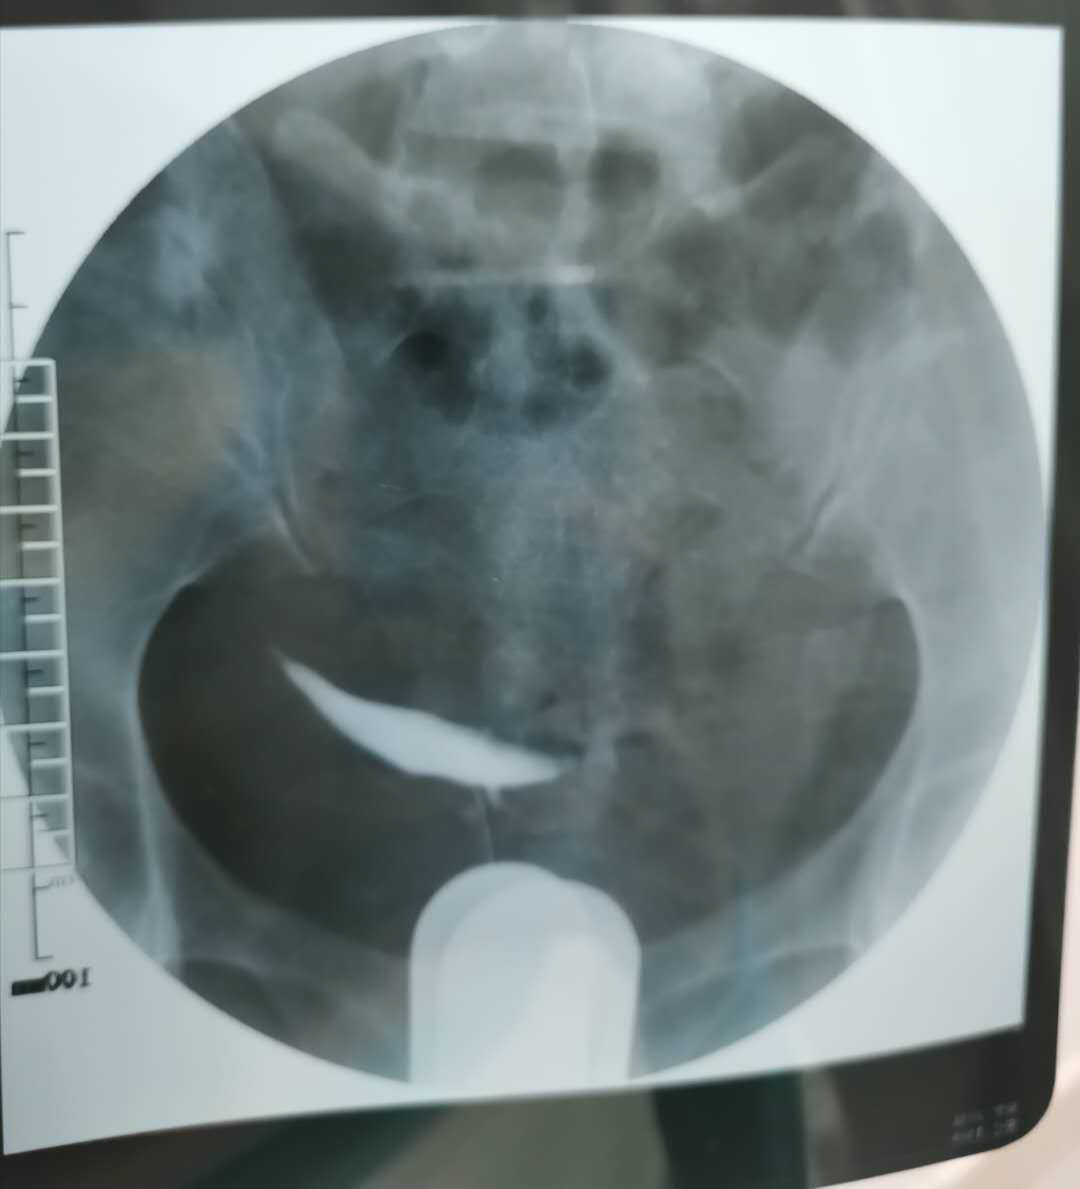

我这个是做了输卵管介入手术,请问输卵管是通了